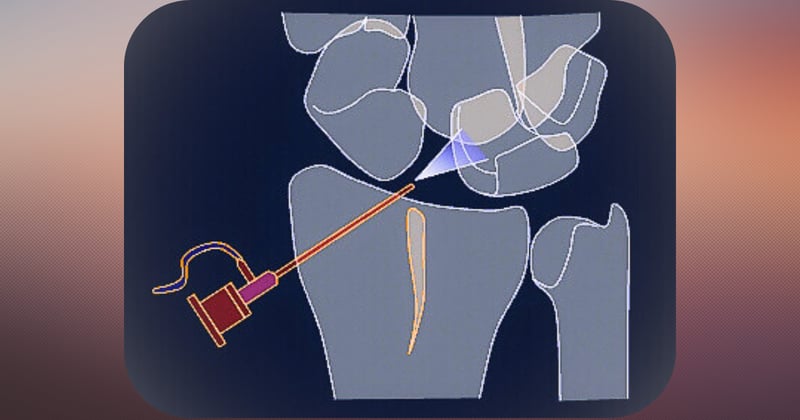

Artroscopia de muñecaArtroscopia de muñeca

+2+2